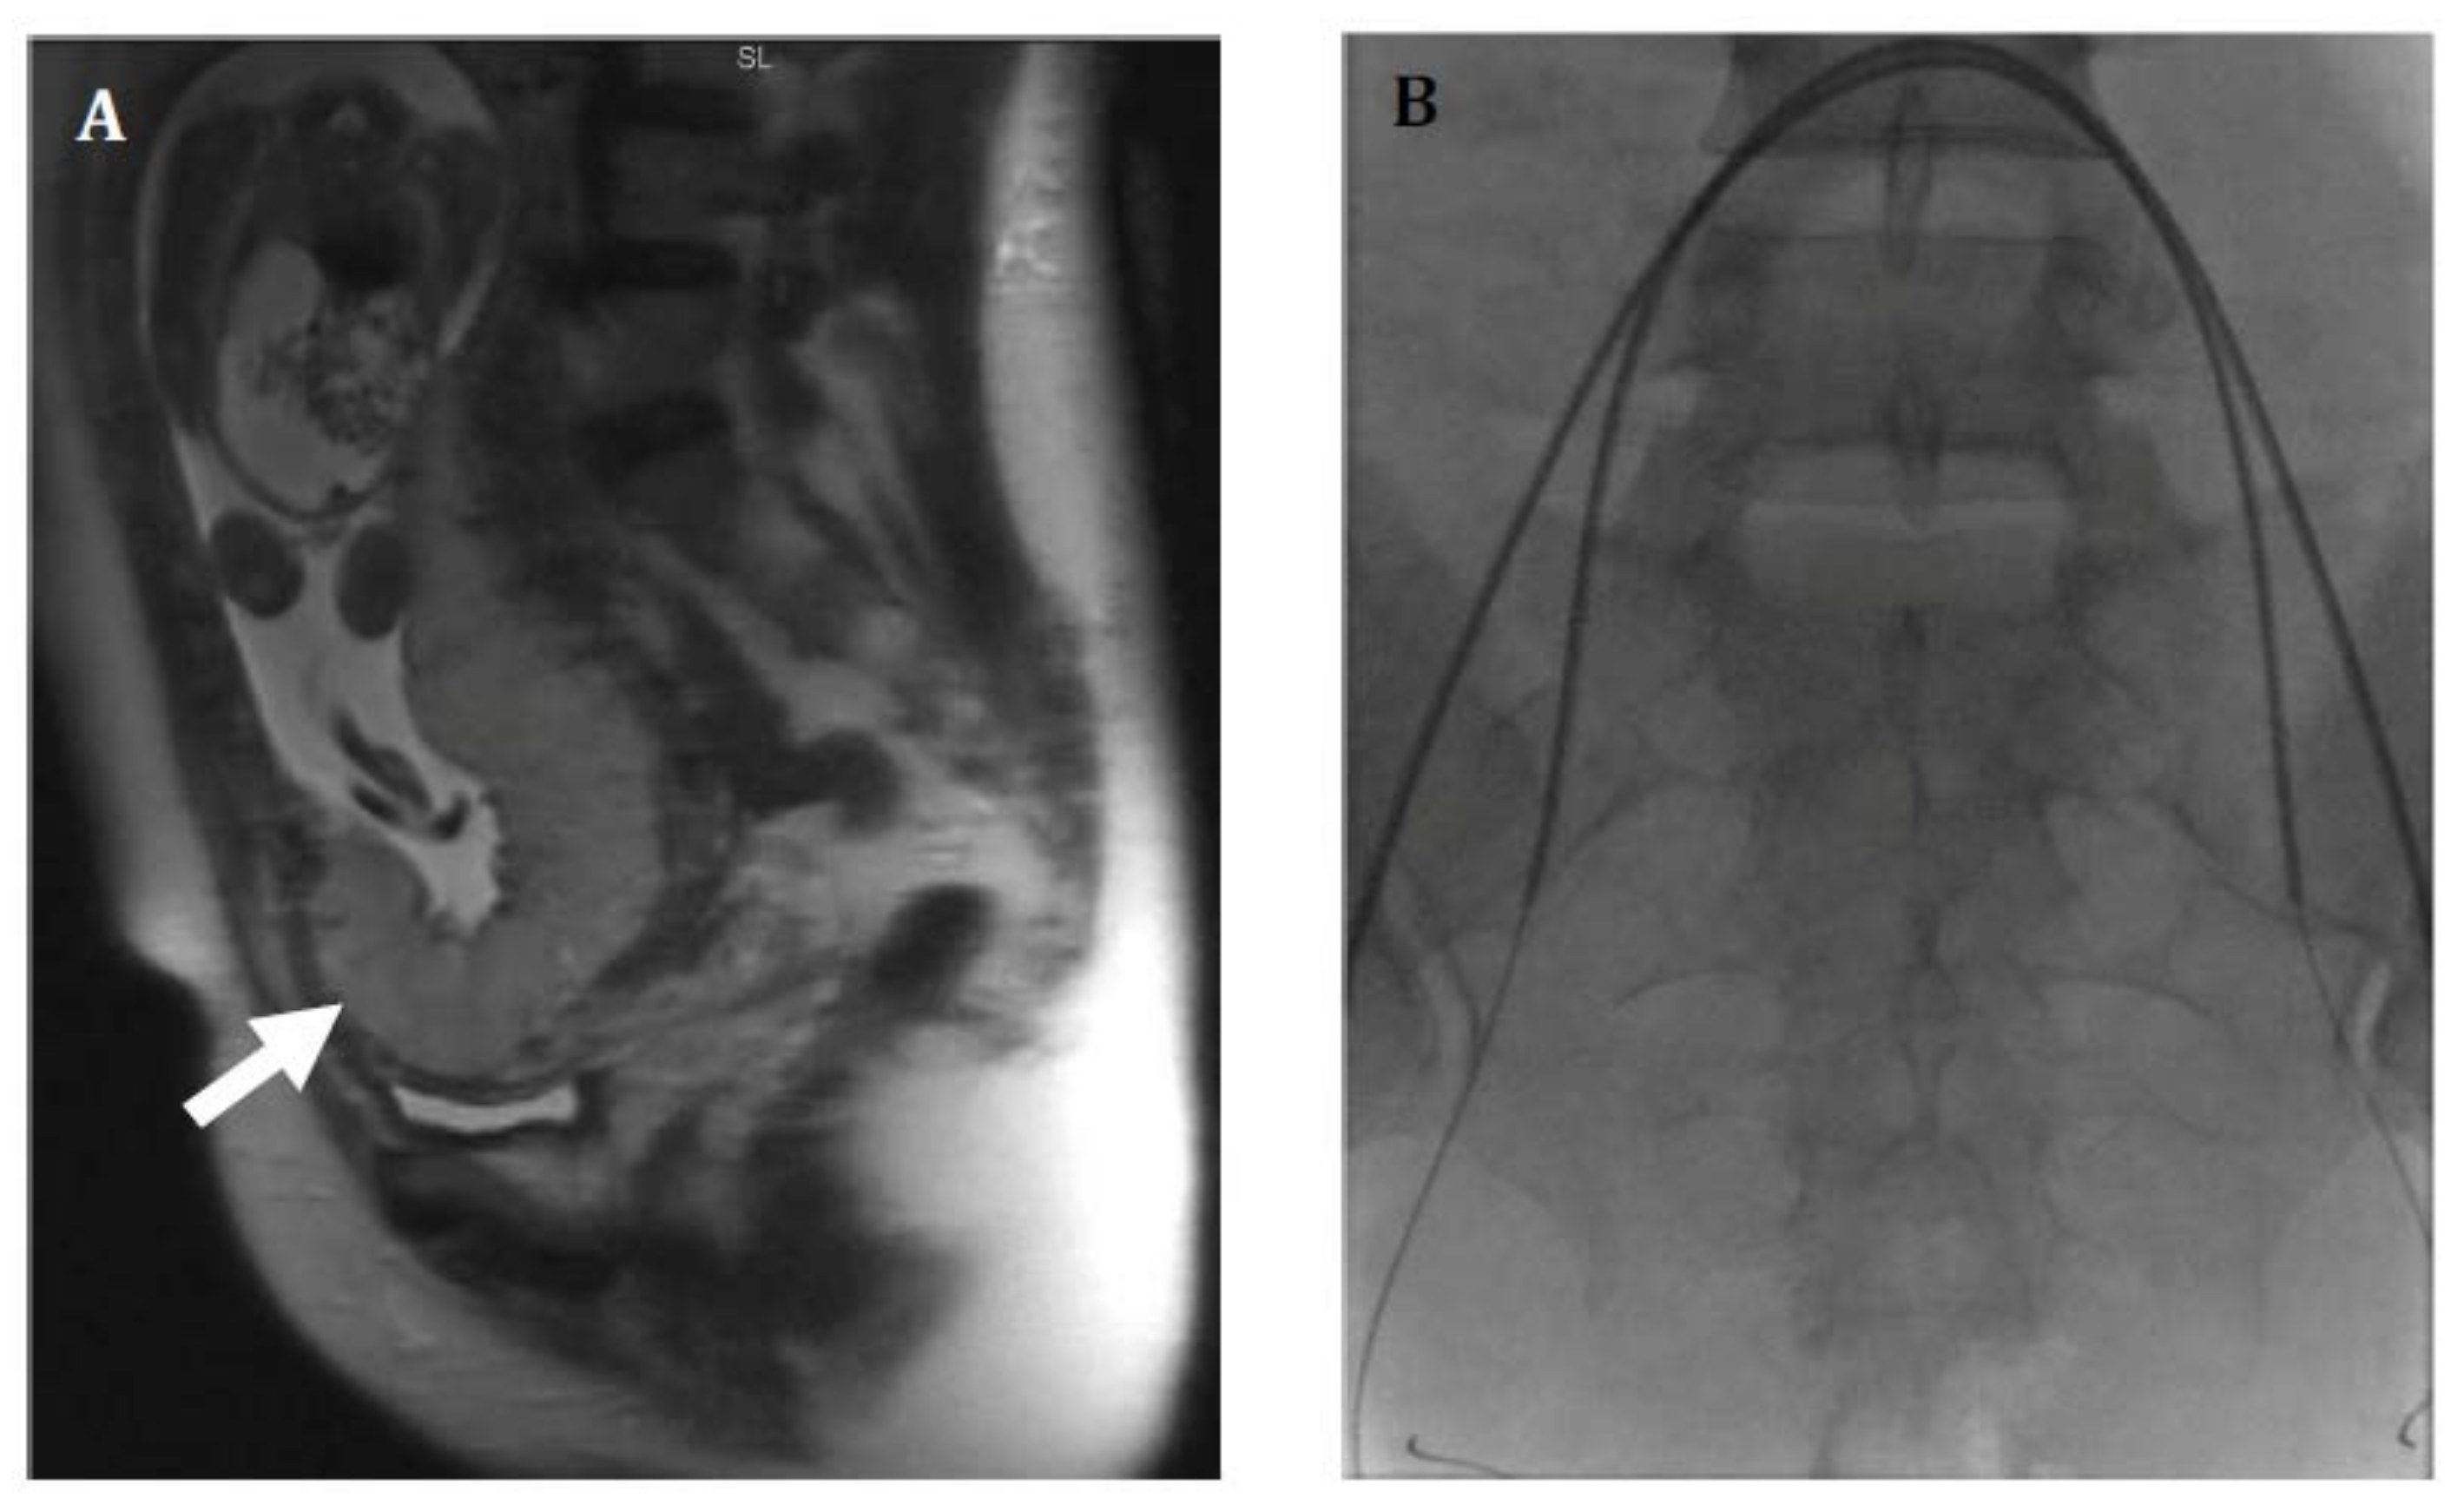

Figure 4.

Thirty-six-year-old female with morbid obesity, severe preeclampsia, and placenta accreta status post cesarean section at 34 weeks. Uterine preservation was performed with incomplete removal of placenta. Patient’s postoperative course was complicated by postoperative bleeding and hypotension requiring massive transfusion and vasopressors. (A) Right internal iliac artery angiogram shows multiple irregular vessels (arrow). Gelfoam embolization of the anterior division was performed until near hemostasis. (B) Post embolization right internal iliac artery angiogram shows no extravasation. Anterior division of left internal iliac artery was also embolized using gelfoam. Despite embolization, patient required hysterectomy for hemorrhagic shock and abdominal compartment syndrome; intraoperative estimated blood loss was approximately 10–15 L. Patient ultimately had a good recovery.